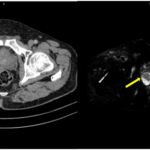

CASE LÂM SÀNG Điều trị bệnh nhân mắc đồng thời hai loại ung thư: Ung thư phổi và ung thư tuyến tiền liệt

CASE LÂM SÀNG Điều trị bệnh nhân mắc đồng thời hai loại ung thư: Ung thư phổi và ung thư...